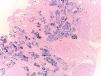

Hematoxylin–eosin stain – 4×. In the sample, 10 glomeruli were identified, 4 of them with global sclerosis (40%) and 1 with segmental sclerosis of a non-specific pattern. The evaluable glomeruli present open capillary loops, preserved mesangial matrix, marked podocyte activation, one with hyalinosis and segmental sclerosis, another with periglomerular fibrosis; without significant alterations in the glomerular basement membrane with the special stains. Casts of brown granular and intracytoplasmic epithelial material predominant in proximal tubules. Signs of acute tubular damage with loss of the brush border, luminal dilation, thinning of the lining epithelium, peeling of cells towards the lumen, in 50% of the sample. Interstitial fibrosis and tubular atrophy, moderate arteries, arterioles and peritubular capillaries, without obvious alterations.

Internal medicina requested evaluation by nephrology due to deterioration of kidney function with a result of proteinuria of 8g in 24h. This way, taking of a renal biopsy is ordered, and is subjected to light microscopy, immunofluorescence and electron microscopy, with a report of podocyte lesion of 70% associated with glomerulosclerosis. focal and segmental (FSGS), severe acute tubular necrosis, interstitial fibrosis with moderate tubular atrophy and pigment casts. Thus, histochemistry was performed with a positive reaction for iron with evidence of intraluminal and cytoplasmic granular deposits in the proximal tubules compatible with hemosiderin and is negative for hemoglobin. During follow-up, she developed severe hyperkalemia refractory to medical management, requiring a single session of renal replacement therapy with hemodialysis. It was determined that the deterioration of renal function was evidenced by pigment cast nephropathy related to sickle cell disease.

Considering the presence of proteinuria in the nephrotic range, the decision was made to perform a renal biopsy, the report of which revealed cortical infarcts due to obstruction of the arterioles and FSGS according to light microscopy. Among the glomerular lesions detected in this patient, FSGS was found to be the most common in patients with sickle cell disease. In a study that included 18 patients, FSGS was confirmed to be the most prevalent histopathological diagnosis, present in 43.7% of cases. Furthermore, collapsing variants with signs of ischemia, membranoproliferative glomerulonephritis in 5 cases and glomerular hypertrophy with or without mesangial hypercellularity and thrombotic microangiopathy (TMA) in 3 patients were reported.5,6

In this particular case, the presence of pigment casts with a negative result for hemoglobin in immunohistochemistry was identified, which is why histochemistry was performed with positive staining for hemosiderin, indicating the presence of a pigment derived from hemoglobin. Pigment cast nephropathy was diagnosed, a condition in which renal function deteriorates due to the toxic effect of pigments containing the heme group. This condition can be caused by various causes, such as rhabdomyolysis (myoglobin pigment), cholestasis (bile acid pigment), and, as in this case, intravascular hemolysis (hemoglobin pigment). It is important to highlight that the presence of hemoglobin casts is rare, and what is described here is the accumulation of hemosiderin in the proximal tubule, as occurs in sickle cell crisis, where there are frequent and persistent episodes of hemoglobinuria.7,8 Furthermore, findings compatible with acute tubular necrosis (ATN) were observed in this patient. It is relevant to note that when ATN occurs alone, without cast nephropathy, special stains in immunohistochemistry do not detect hemoglobin and myoglobin, as happened in this case. It is important to keep in mind that, in case series of patients with pigment cast nephropathy, 100% of cases present acute tubular injury.9–11